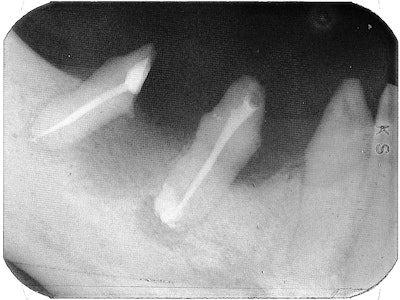

Root canal therapy was done on the mesial roots of both molars, and the mesial canals were obturated with Pulpdent Root Canal Sealer (Pulpdent) using the Pressure Syringe technique. The teeth were hemisected and the distal roots were removed.

This enabled us to use the natural roots of his teeth for abutments instead of placing implants, thus sparing the patient from the surgery.

A temporary was made until healing occurred. Then a fixed bridge was crafted. The radiograph below was taken seven years later and shows healthy bone and the bridge in place.